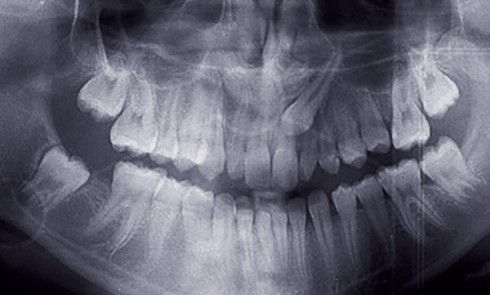

Examen initial Âgée de 15 ans, cette patiente est adressée par son chirurgien-dentiste pour un avis orthodontique car une décision...